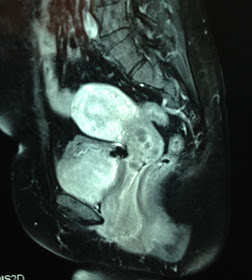

MRI 1, MRI 2 in sagittal section, this tumor is like a second uterus.